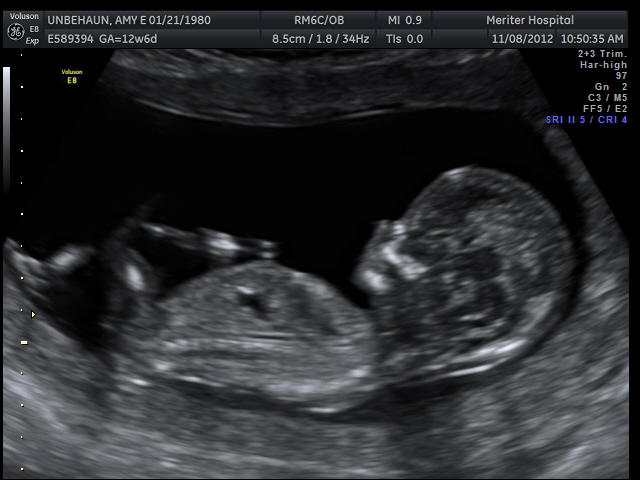

Nub guess please - 12w6d u/s